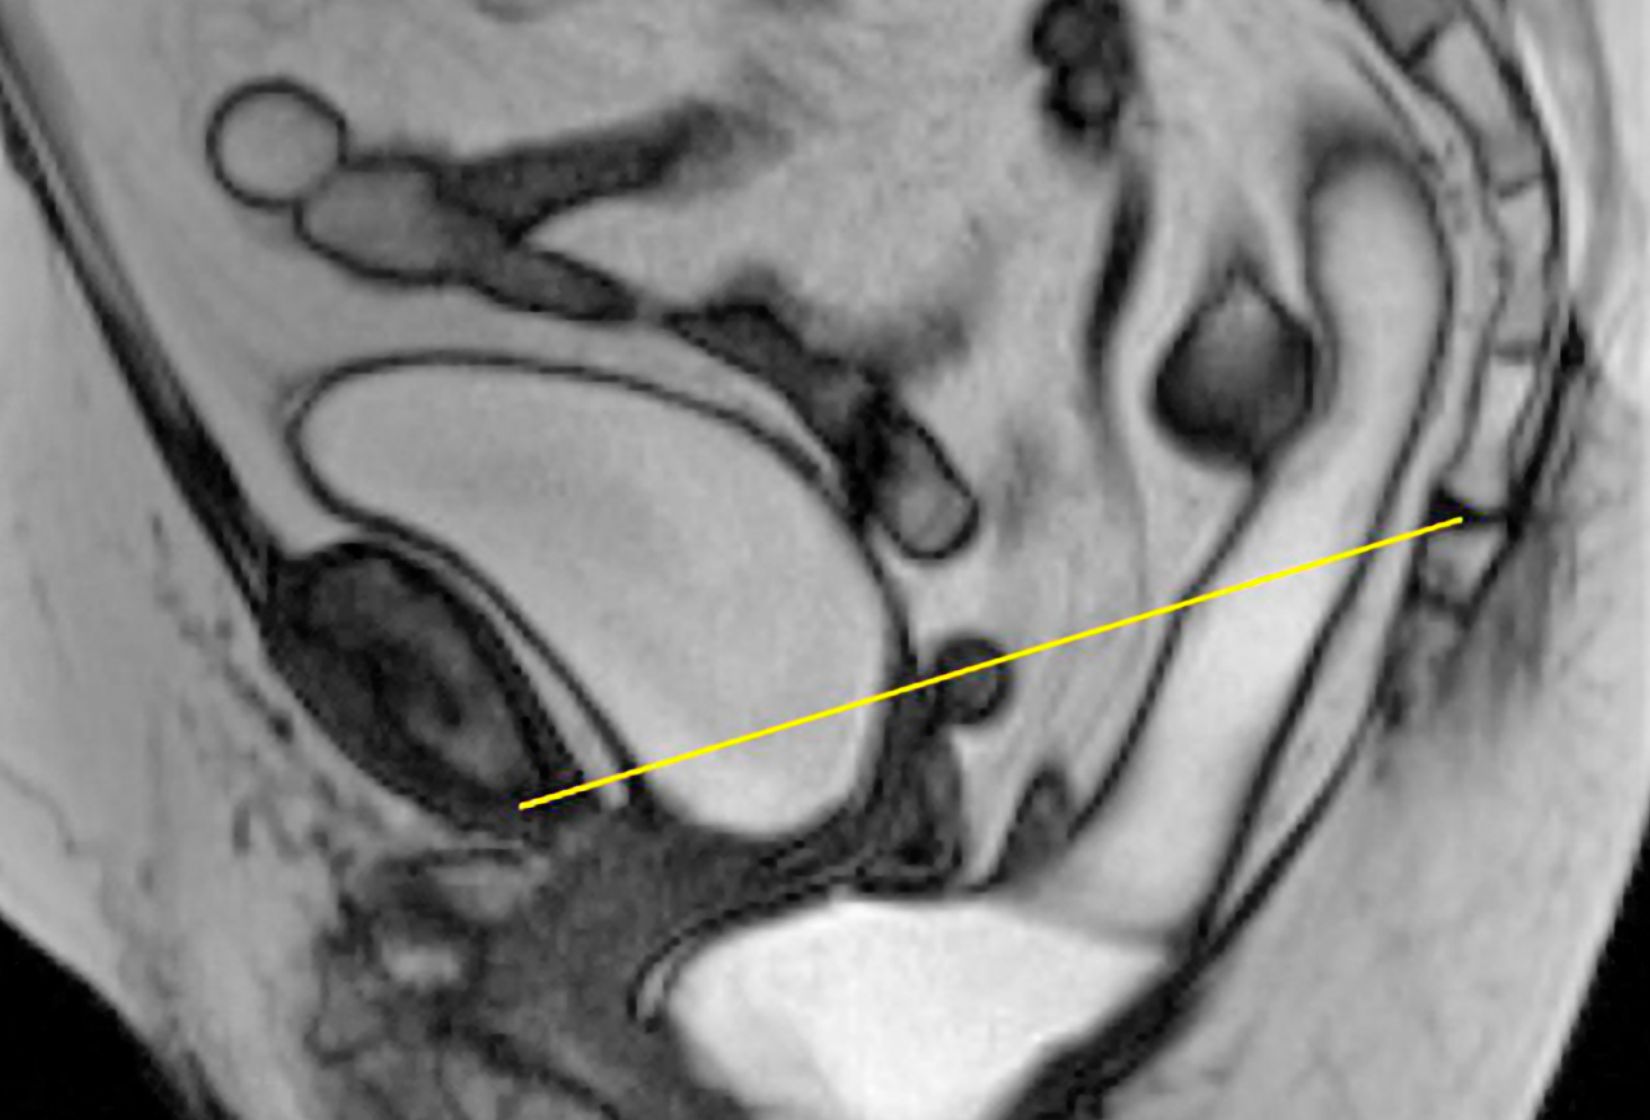

Neben der Standard-CT und -MRT-Untersuchung des Beckenbodens (siehe auch CT/ MRT) , kann bei speziellen Fragen auch eine dynamische Beckenboden-Untersuchung im MRT erfolgen. Die Patientin/ der Patient muss hierzu nicht nüchtern sein und es wird kein intravenöses Kontrastmittel gegeben. Eine Sedierung bei Platzangst ist nur eingeschränkt möglich , da bei dieser Untersuchung die Kooperation und Befolgen von Anweisungen im Gerät nötig sind. Die Untersuchung wird nach ausführlicher Anamnese und Erklärung und Übungen im Liegen durchgeführt.